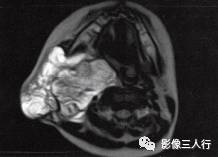

A.B.MRI T1WI显示右侧上颈部大片混杂低信号,其内见蜂窝状更低信号,肌间隙显示不清,并见点、线状高信号。咽、喉、气管受压移位;C〜F.T2WI的横断面、冠状面病变表现为不均匀高信号,形态不规则,可见病变向上、下,向左、右延伸,有“见缝就钻”的特点,气管及周围软组织受压移位

2.T1WI显示右侧颈部大片混杂低信号,其内见到多个类圆形囊性低信号。

3.T2WI病变表现为不均匀的高信号,形态不规则,其内可见分隔,具有“见缝就钻”的特点。气管及周围软组织受压移位。